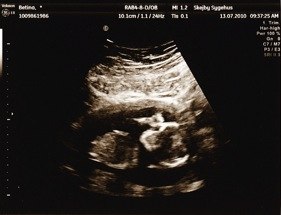

Var til nf scanning i dag, hold da op det er jo helt fantastisk at se den lille hygge sig inde i maven og høre hjertet slå.

Min termin blev rykket fire dage frem :-) så er ikke 12+5 som jeg troede i morges men 13+2 ihh det er så dejligt at få at se hvad maven gemte på, kan slet ikke vente til næste scanning :-)

Alle tal var helt fine, så risiko for down syndrom er meget meget lav. Kunne ikke lade vær med at knipe en lille tåre :-)